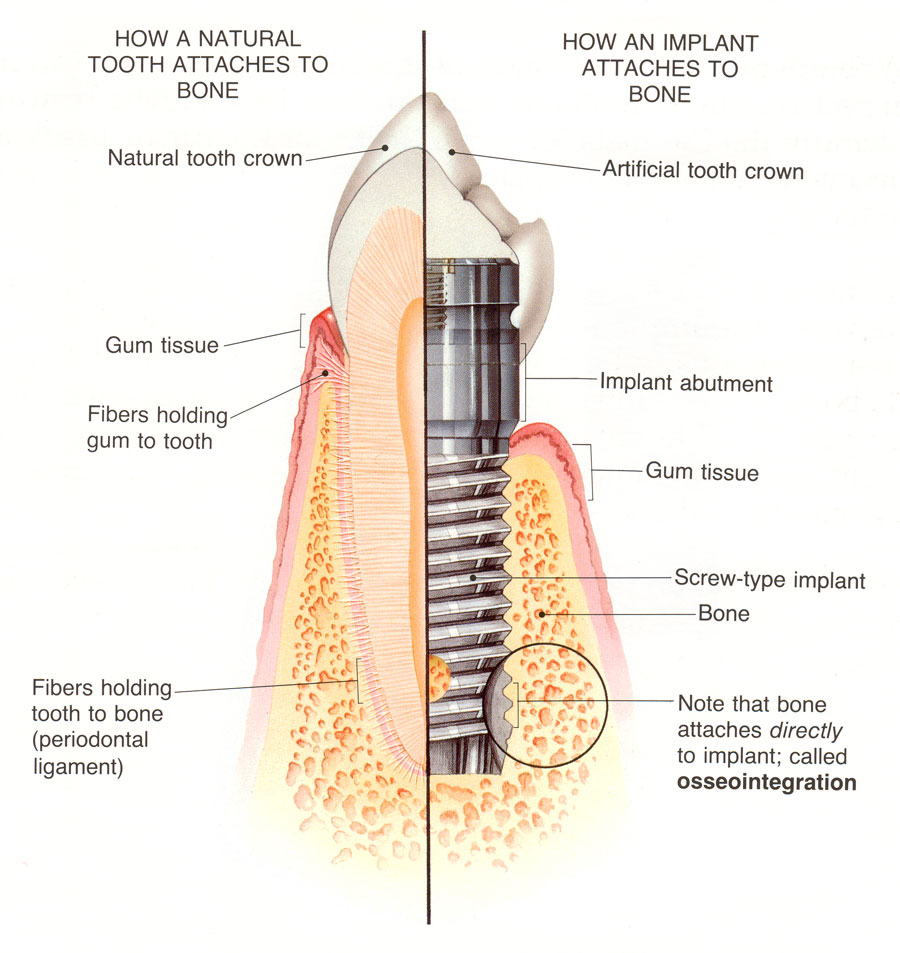

Do Dental Implants Really Mimic Natural Teeth?Healthy Body, Healthy …

What is a Dental Implant? | DDi

Dental Implant, Single Tooth

How dental implants work – Dental News Network

How do dental implants work? ⋆ Dental House

Dental Implants Portland OR | What Are Dental Implants